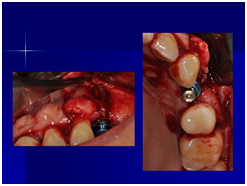

98/01/08經過三個半月做右下第一小臼齒的二階暴露,發覺鄰牙的植體高度竟已掉下來

980305幫患者補角化牙齦並翻開清除發炎組織,期待能阻止繼續骨破壞

a. 右下第一小臼齒的植體位置,放置得太低;若能將此顆植體上的polished surface放在骨平面上,應可減少之後將鄰近植體骨高度往下帶的情形。

b. 近遠心間距在植體間的間距需求為2-3 mm(指最終第一小臼齒植體與鄰近植體間距),比當初第一小臼齒尚未拔除時,是自然牙與植體的間距需求更大(最少為1.5mm);因此造成骨破壞的因素之一,也可能和鄰近植體的間距不足有關。

c. 由98/3補皮的臨床照片,推敲最初原本後面的三顆植體有可能放置在較頰側,但由於鄰接面有足夠的骨頭高度,所以牙齦仍被支撐在恰當位置,因此臨床上無特別發現;但當根裂拔牙後,鄰接面的高度一掉,很快地原本頰側骨頭不足的問題,便很快的浮現出來;接著螺紋跑出,而患者又是牙周病的高風險群,當時身體狀況不佳,口腔衛生照顧不足,都加乘造成骨破壞進一步進行。